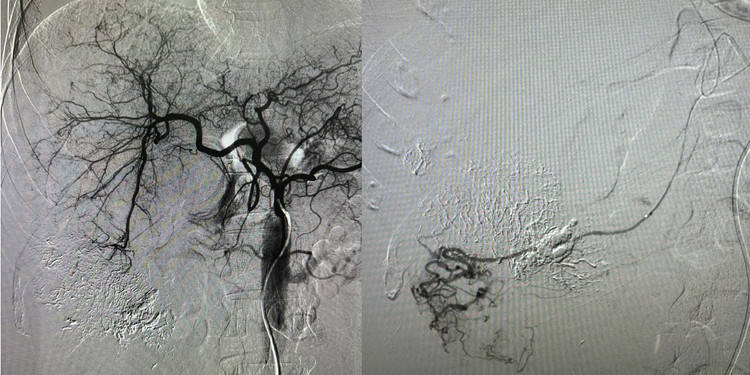

u-gan-vo-1.jpg

Nút mạch cho bệnh nhân u gan vỡ - Ảnh BVCC

Kỹ thuật nút mạch gan được thực hiện nhằm cầm máu tổn thương gan qua đường mạch máu mà không cần phẫu thuật mở. Đây là phương pháp ít xâm lấn, giúp kiểm soát tình trạng chảy máu hiệu quả và hạn chế tối đa nguy cơ biến chứng trong giai đoạn cấp tính.

Sau khi tiếp nhận, bệnh nhân nhanh chóng được hội chẩn đa chuyên khoa gồm chẩn đoán hình ảnh, ung bướu và hồi sức cấp cứu. Quyết định can thiệp nút mạch gan được đưa ra sau khi đánh giá tình trạng mất máu trong ổ bụng và tổn thương tại khối u.